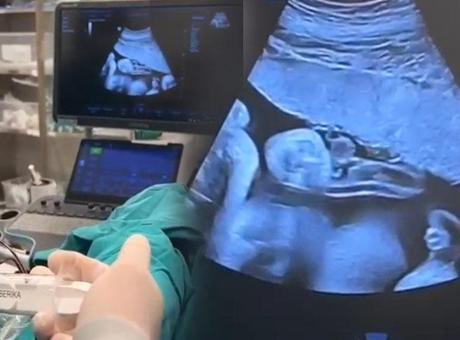

Bebeğini kaybetti, 2'nci kez hamile kalınca doktorlar fark etti! 'Anne karnında transfer ettik'

Bütün işlemlerin ultrason eşliğinde yapıldığını ve bebeğin sağlık durumunun iyi olduğunu belirten Dr. Bülent Babaoğlu, şunları söyledi:

Rezalet görüntü! Tuvaletin yanındaki şalgam imalathanesi kapatıldıAnne karnında bebeğe kan nakli yapmayı önerdik, uygun olduğunu gördük. Aile de bunu kabul etti. 31'inci haftada uygun şartlar, özel kan ayarlandıktan sonra işlemi uygun protokole göre uyguladık. Bütün işlem ultrason eşliğinde yapılıyor. Ufak bir iğneyle kordona ulaşıyoruz, bebeğe kan götüren damara. Oradan küçük miktarda kan alıp, hazırda bekleyen laboratuvar bebeğin kan grubu, kan değerlerini bize hızlıca çalışıp söylüyor. Biz de gelen sonuca göre bebeğe vermemiz gereken kan miktarını ayarlıyoruz. Yapılan hesaplamalarda uygun görülen 90 mililitrelik kanı biz anne karnında transfer ettik. Transfer sonrası takiplerimiz de gayet uygun. Anne de bebek de şu an için sağlıklı. Böyle durumlarda bazen nadiren ikinci bir kez daha kan transferi ihtiyacı olabiliyor. Bunun için biz de zaten hastamızı sıklıkla takip ediyoruz. Anne karnında gayet iyi. Doppler muayeneleri normal. Beklenen kilosunun üzerinde. Yani sağlıklı bir bebek bekliyoruz hayırlısıyla."